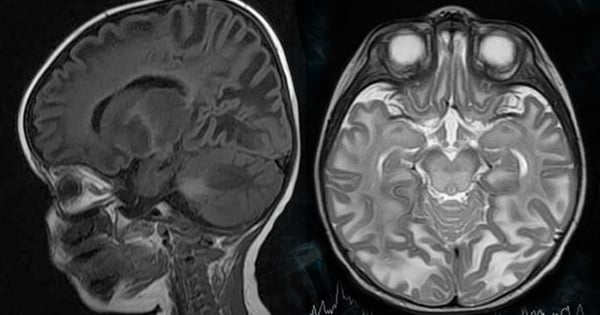

Canavan Disease Investigator at the Li Weibo Institute